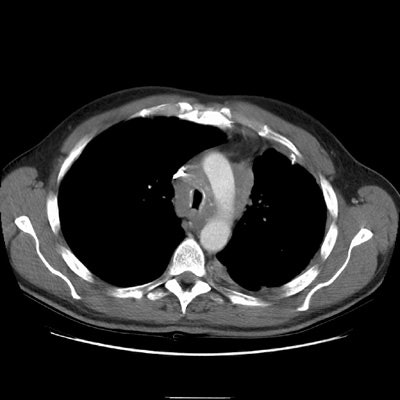

CT reveals an infiltrative mediastinal soft tissue abnormality encasing and narrowing the trachea.